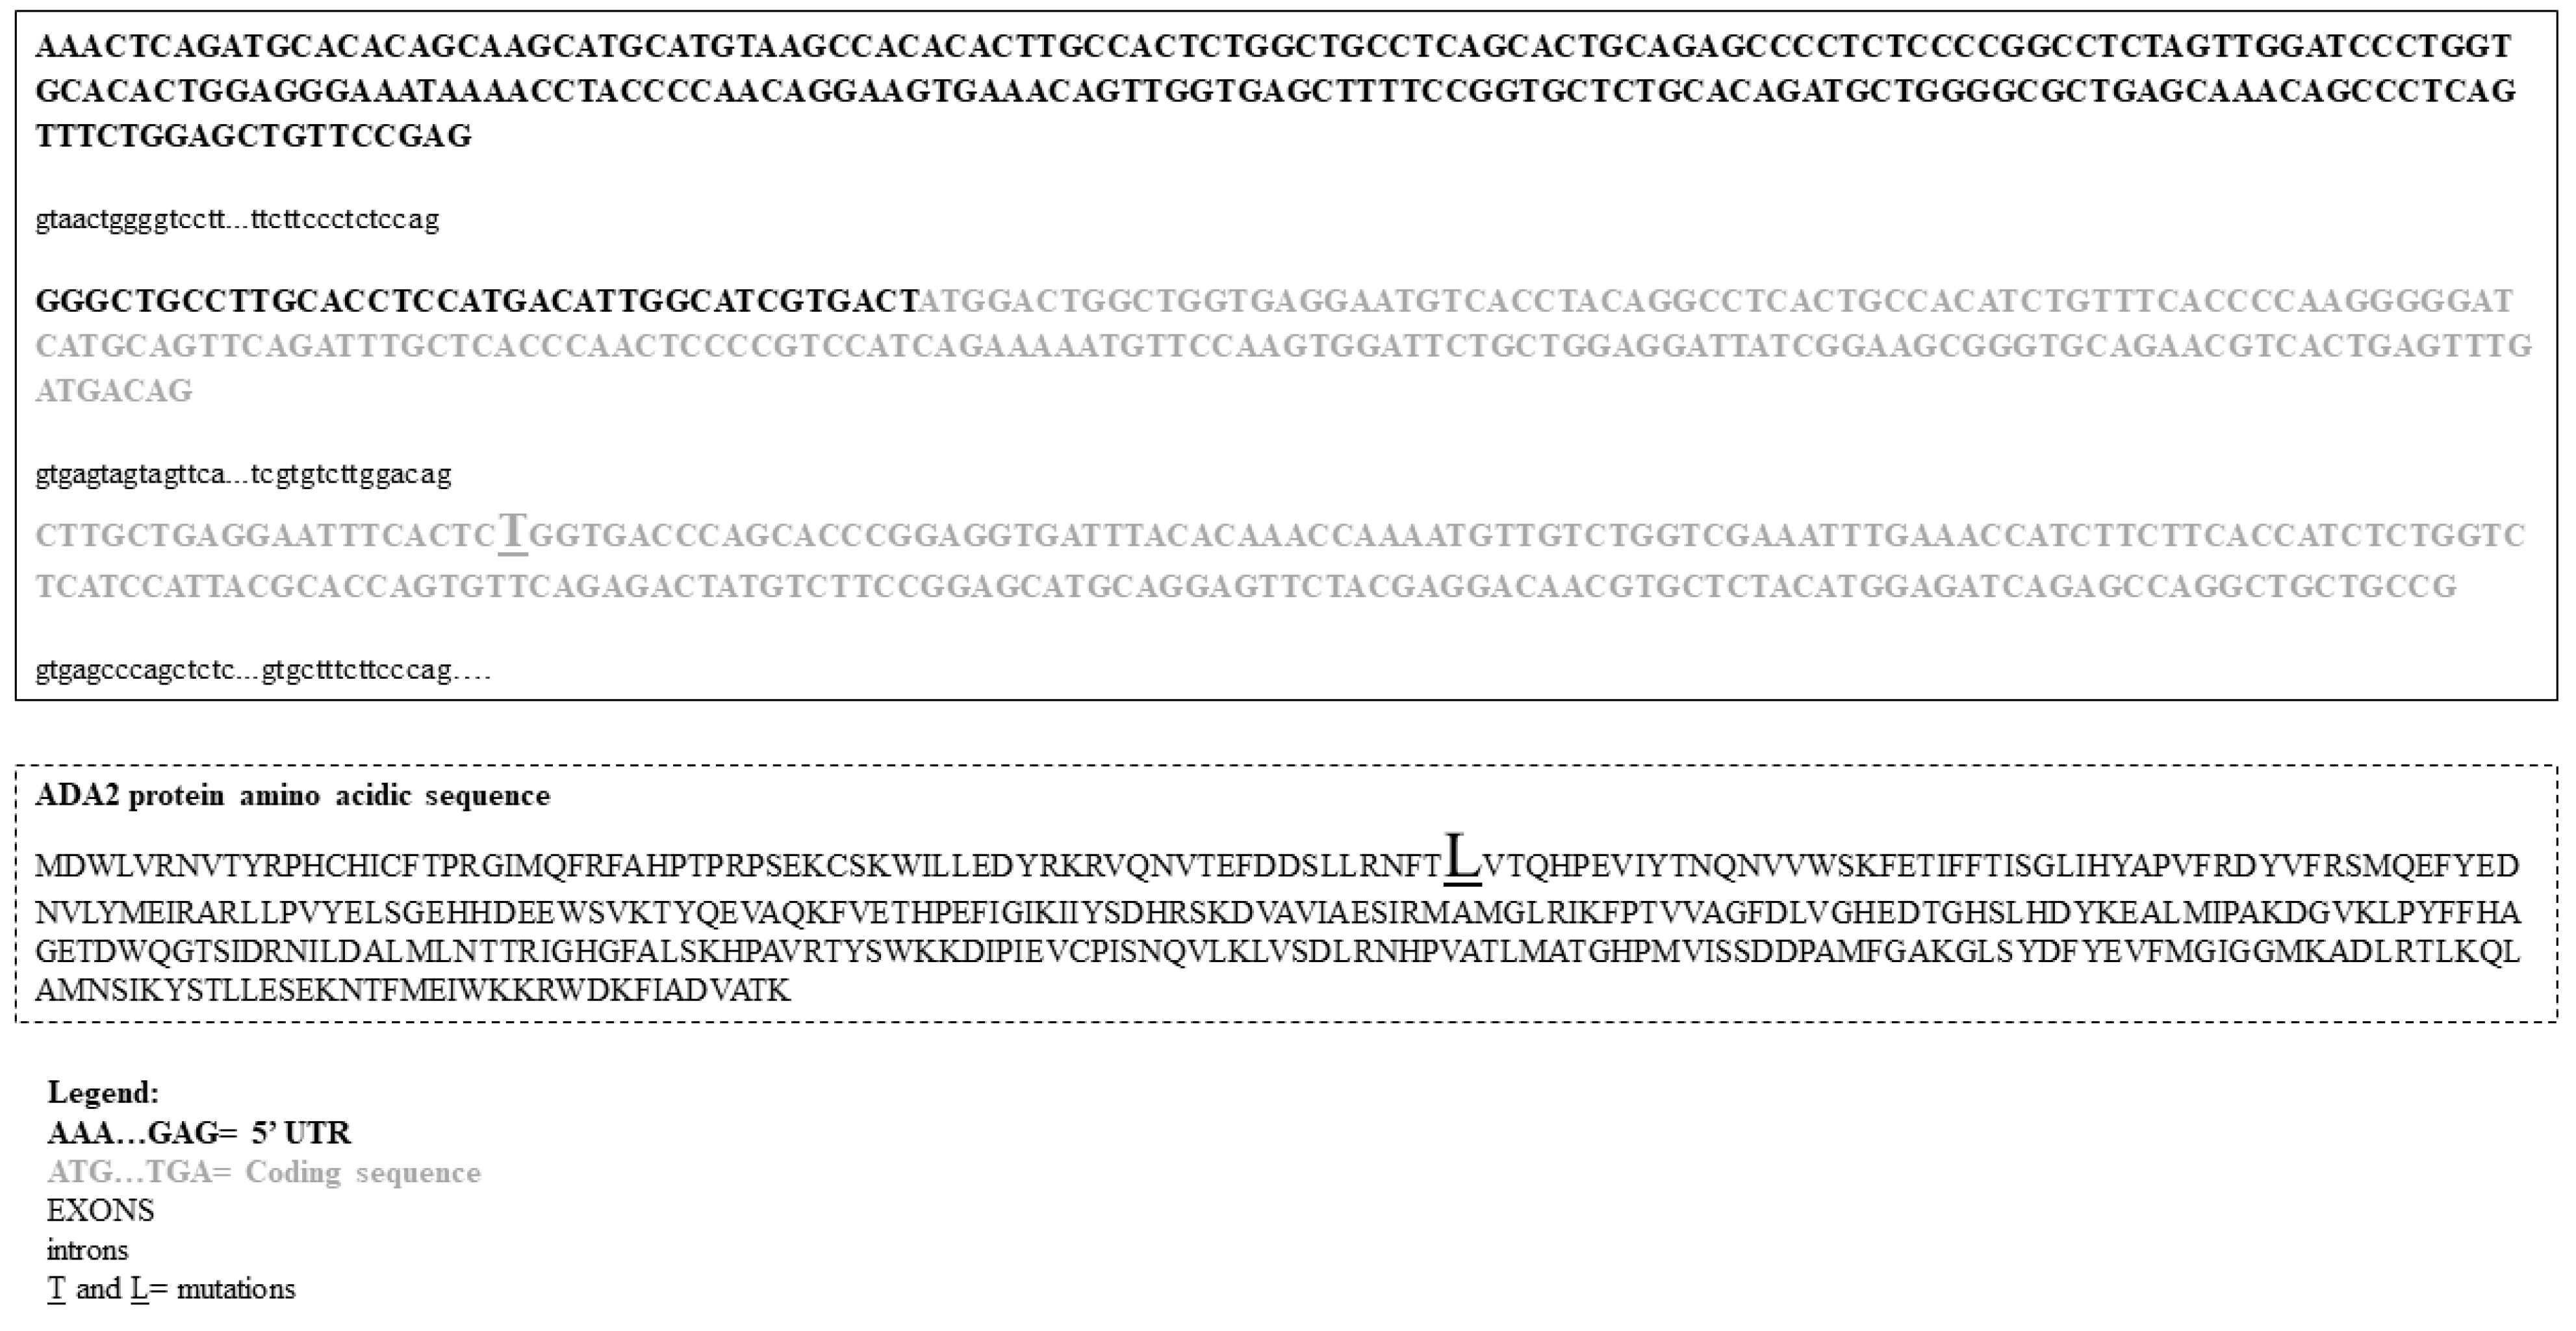

3.2. Mutational Analysis

4.4. Mutational Analysis